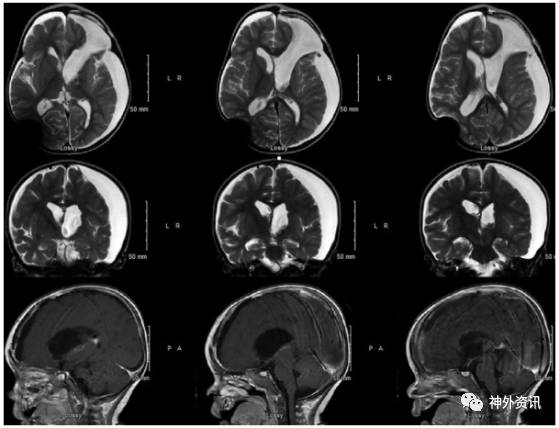

图2. 脑室内ATRT全切除术后1月MRI复查,未见肿瘤影。